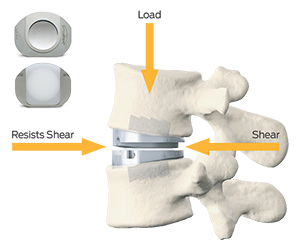

The prodisc L implant has been designed to maintain the physiological range of motion in the spine. The implant was developed using the clinically proven ball and socket concept used in joint replacement implants for over 40 years. The prodisc L implant is composed of three components – two cobalt chrome alloy (CoCrMo) endplates and an ultra-high molecular weight polyethylene (UHMWPE) inlay.

Mechanism of Action

The prodisc implant is a ball and socket design with a fixed center of rotation. This patented design has been in clinical use since 1990 and utilized across the entire product platform. The fixed center of rotation allows physiological range of motion while providing stability to the spine and significantly reducing reoperations at the adjacent levels.